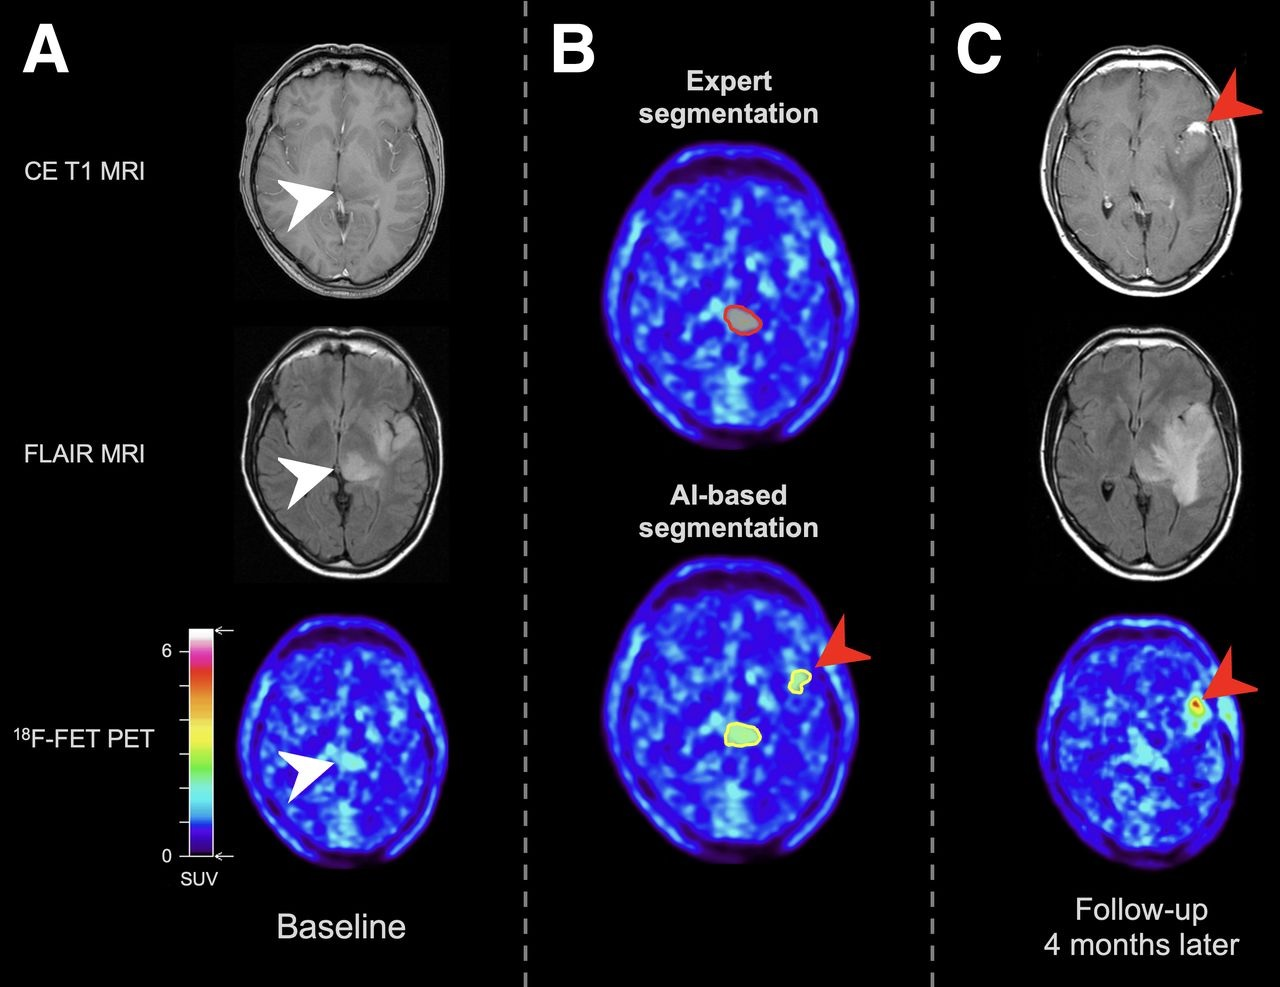

Axial (top) and coronal views (bottom) from 3-year-old boy with a grade IV atypical teratoid/rhabdoid tumor. A large intraventricular contrast-enhancing tumor mass (left column) was discovered preoperatively. Postoperative MRI identified a contrast-enhancing residual tumor inferiorly in the resection cavity (thin yellow arrow). An additional small residual tumor (red arrow) was identified only by FET-PET. Complete resection was obtained by removing both residual tumor masses. The patient received radiochemotherapy and is in long-term remission. Images courtesy of JNM.Early postoperative FET-PET/MRI achieved lesion specificity of 100%, compared with 75% for MRI alone. FET-PET/MRI also had better accuracy (87%) than MRI alone (77%). Regarding sensitivity, MRI alone (80%) was superior to FET-PET/MRI (73%).